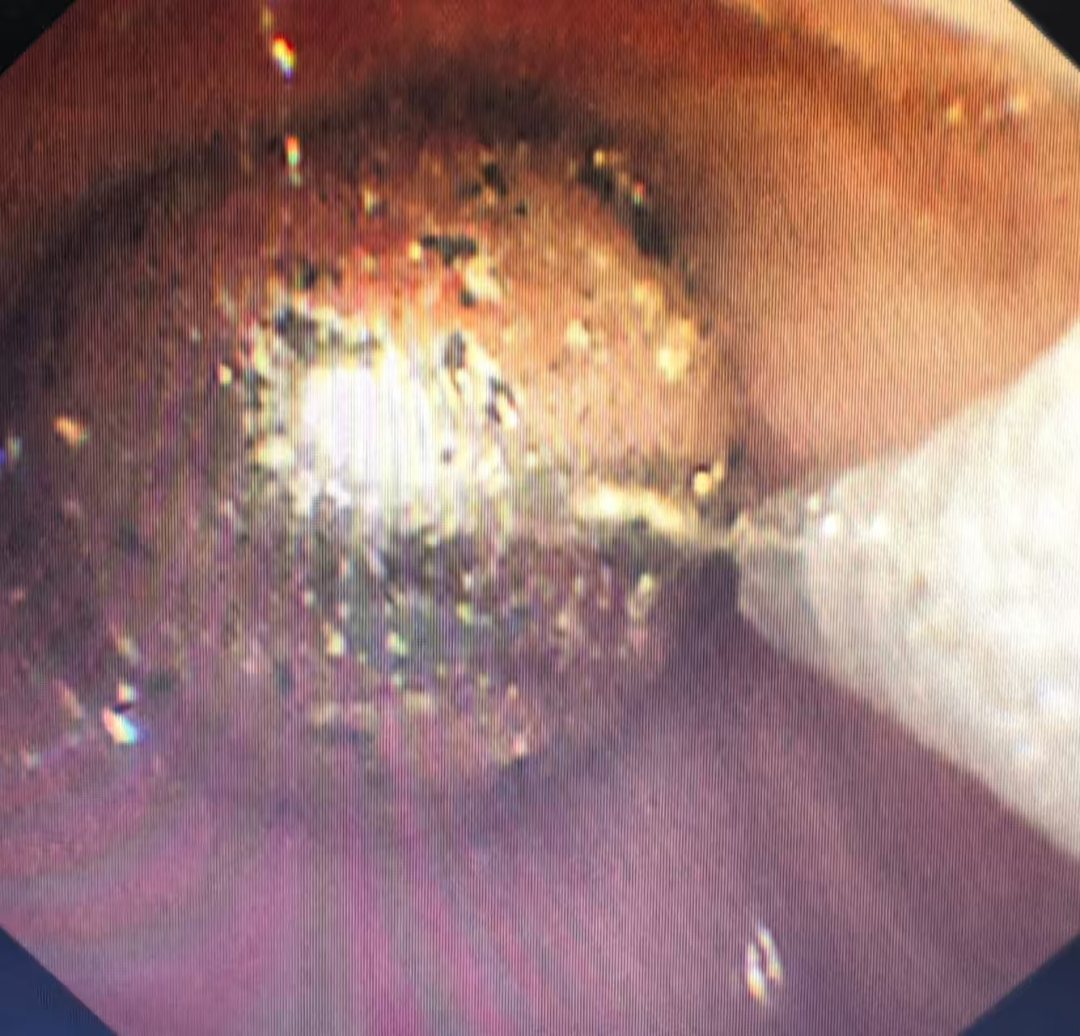

多学科团队面临严峻挑战:通过支气管镜下所见患儿声门水肿,金属珠子表面光滑,稍有不慎都有可能滑落再次阻塞气道。麻醉团队通过精准镇静,呼吸三科内镜团队娴熟操作支气管镜,在视野狭窄的气道内通过异物网篮成功将金属珠完整取出!术后患儿生命体征平稳,转入PICU进一步观察。